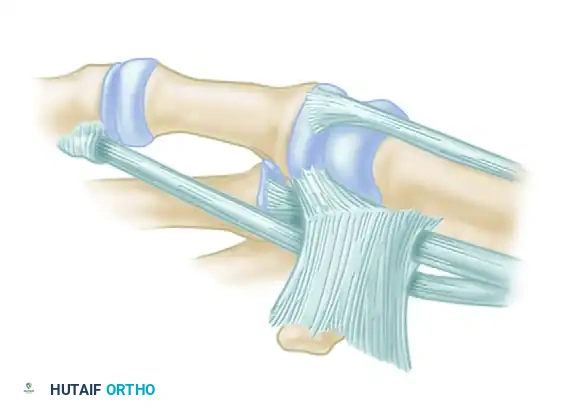

- Final Weave: Pass the remaining tail beneath or through a short split in the intact FCR tendon just proximal to the trapezium. Route it back across the radial margin of the joint to insert into the metacarpal periosteum. Suture the tendon securely at every point where its direction changes.

Figure: Schema of volar and radial ligament reconstruction. The complex course of the tendon strip creates robust reinforcement in the volar, dorsal, and radial aspects of the joint.

Intraoperative view of the final tendon weave and capsular reinforcement.